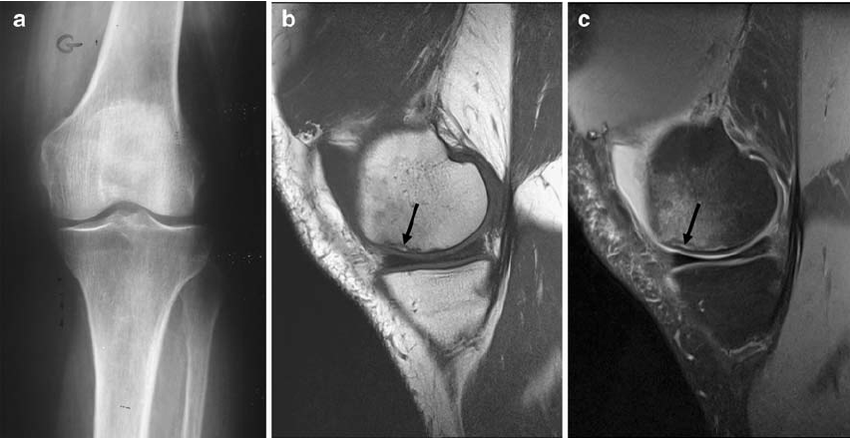

1) X-ray: Commonly used.

2) CT scan (Computed tomography): Clearly identify the exact positon number, size of fracture.

3) MRI (Magnetic resonance Imaging):can show image in any place with clear.